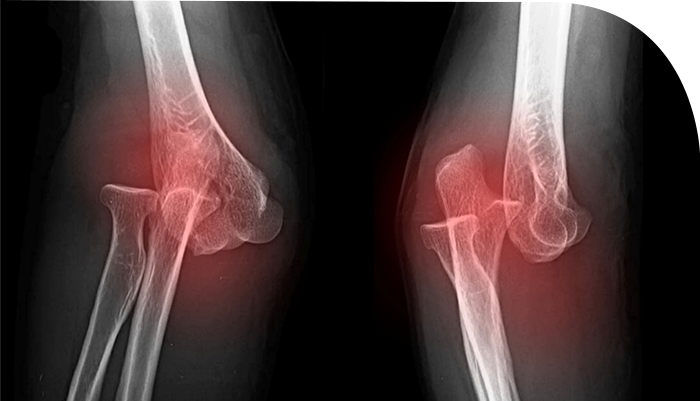

°ñÀýÀ̶õ ¿ÜºÎÀÇ Ãæ°Ý¿¡ ÀÇÇØ »À°¡ ºÎ·¯Áö´Â °ÍÀÔ´Ï´Ù. »À, °ñ´ÜÆÇ, °üÀý¸éÀÇ ¿¬¼Ó¼ºÀÌ ¿ÏÀü ȤÀº ºÒ¿ÏÀüÇÏ°Ô ²÷¾îÁø »óÅÂÀÔ´Ï´Ù.

°ñÆí¼ö¿¡ µû¶ó ºÐ¼â°ñÀýÀÌ µÉ¼öµµ ÀÖ°í, ºÐÀý¼º °ñÀýÀÌ µÉ ¼öµµ ÀÖ½À´Ï´Ù. °ñÀý¸é ¹æÇâ¿¡ µû¶ó ´Ù¾çÇÑ °ñÀý ÇüŰ¡ ¹ß»ýÇÒ ¼ö ÀÖ½À´Ï´Ù.

»óÁö ȤÀº ÇÏÁöÀÇ ½Å°æ ¹× Ç÷°üÀÇ ¼Õ»óÀÌ µ¿¹ÝµÉ ¼ö ÀÖ¾î, Á¶±â¿¡ Áø´ÜÇÏ°í ºü¸¥ °ñÀý Ä¡·á°¡ ÇÊ¿äÇÕ´Ï´Ù.